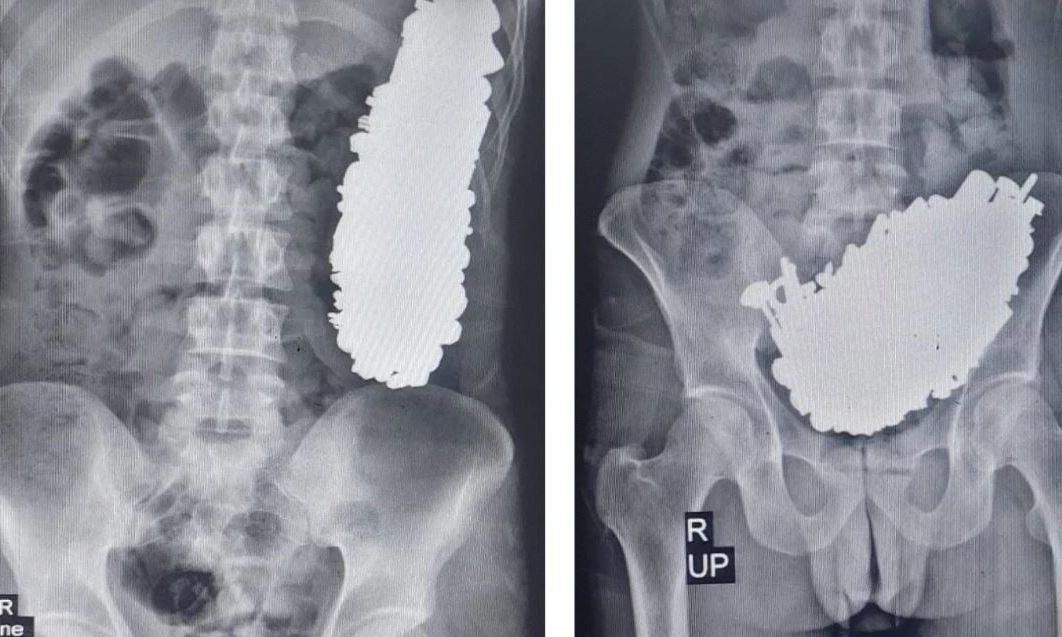

Ο ασθενής είχε τις αισθήσεις του και είχε σταθερά ζωτικά σημεία. Στην ακτινογραφία και την ενδοσκόπηση του ασθενούς, εντοπίστηκαν πολλαπλά μεταλλικά αντικείμενα μέσα στο στομάχι του ασθενούς, προκαλώντας απόφραξη της γαστρικής εξόδου.

Ο ασθενής υποβλήθηκε σε επέμβαση γαστροστομίας και αφαιρέθηκαν από το στομάχι 452 βίδες, παξιμάδια, κλειδιά, πέτρες και άλλα μεταλλικά μέρη βάρους 3 κιλών.